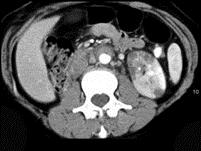

问题 女,29岁,尿频、尿痛伴寒战高热3天。尿检:白细胞(+++),请结合图片作出最佳诊断 ( )

选项 A、左侧肾结核 B、左侧肾囊肿合并感染 C、左侧急性肾盂肾炎 D、左侧肾脓肿 E、左侧肾癌

答案 C